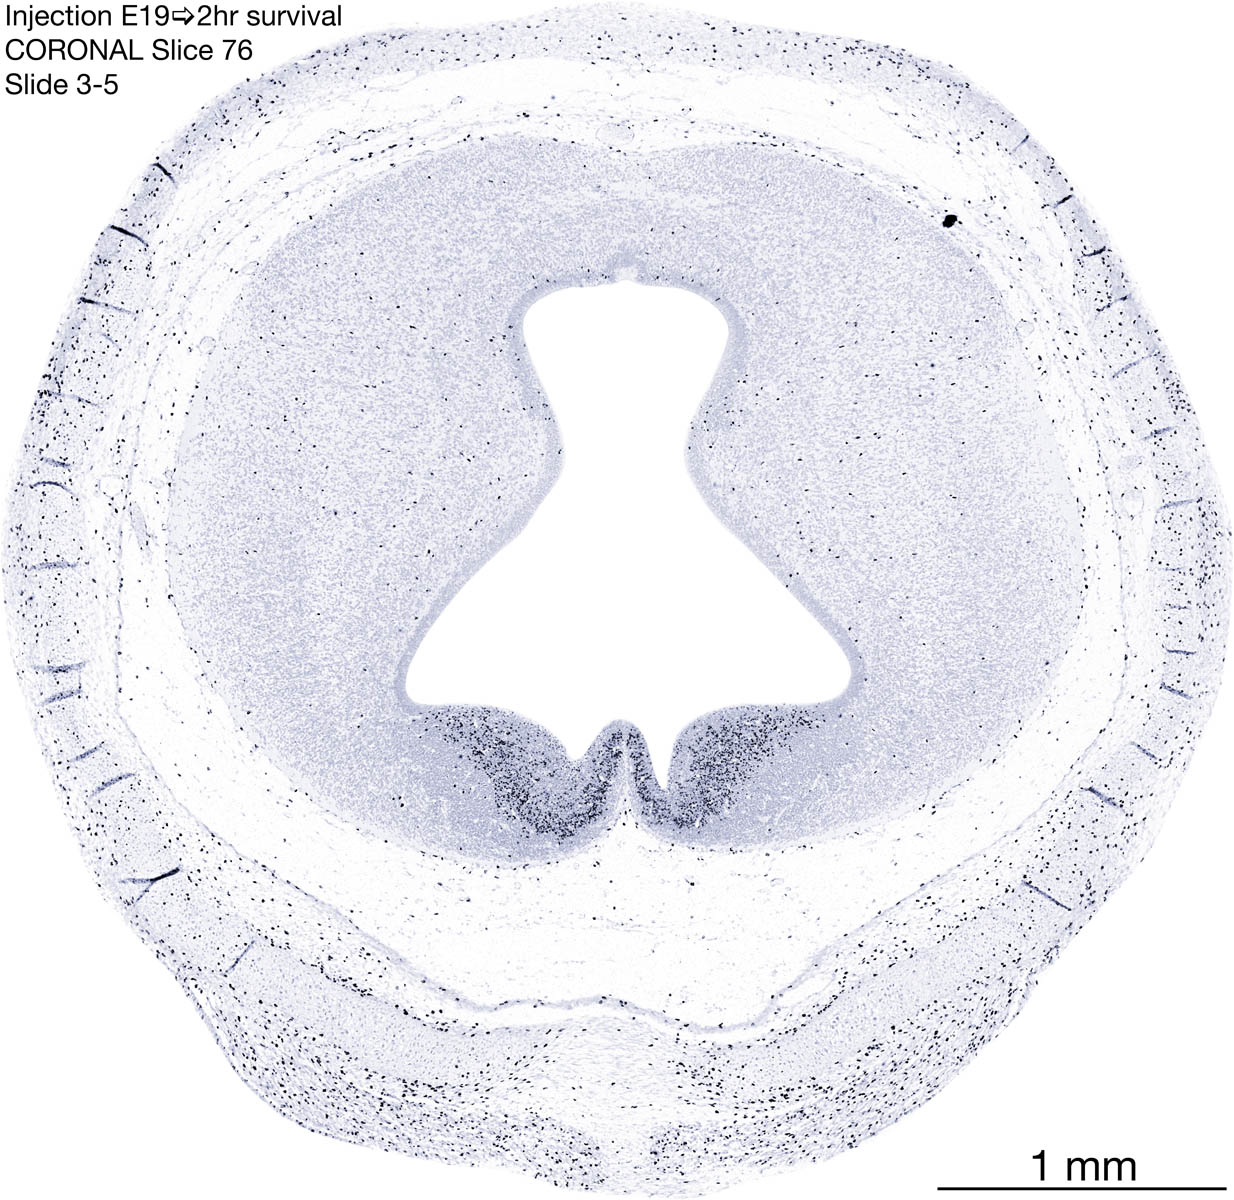

E19 2hr Survival Archived Images-Coronal The following images are from a paraffin-embedded coronally-sectioned head of an E19 rat embryo exposed to tritiated thymidine 2 hours before death. Download: Large | High Res Download: Large | High Res Download: Large | High Res Download: Large | High Res Download: Large | High Res Download: Large | High Res Download: Large | High Res Download: Large | High Res Download: Large | High Res Download: Large | High Res Download: Large | High Res Download: Large | High Res Download: Large | High Res Download: Large | High Res Download: Large | High Res Download: Large | High Res Download: Large | High Res Download: Large | High Res Download: Large | High Res Download: Large | High Res Download: Large | High Res Download: Large | High Res Download: Large | High Res Download: Large | High Res Download: Large | High Res Download: Large | High Res Download: Large | High Res Download: Large | High Res Download: Large | High Res Download: Large | High Res Download: Large | High Res Download: Large | High Res Download: Large | High Res Download: Large | High Res Download: Large | High Res Download: Large | High Res Download: Large | High Res Download: Large | High Res Download: Large | High Res Download: Large | High Res Download: Large | High Res Download: Large | High Res Download: Large | High Res Download: Large | High Res Download: Large | High Res Download: Large | High Res Download: Large | High Res Download: Large | High Res Download: Large | High Res Download: Large | High Res Download: Large | High Res Download: Large | High Res Download: Large | High Res Download: Large | High Res Download: Large | High Res Download: Large | High Res Download: Large | High Res Download: Large | High Res Download: Large | High Res Download: Large | High Res Download: Large | High Res Download: Large | High Res Download: Large | High Res Download: Large | High Res Download: Large | High Res Download: Large | High Res Download: Large | High Res Download: Large | High Res Download: Large | High Res Download: Large | High Res Download: Large | High Res Download: Large | High Res Download: Large | High Res Download: Large | High Res Download: Large | High Res Download: Large | High Res Download: Large | High Res Download: Large | High Res Download: Large | High Res Download: Large | High Res Download: Large | High Res Download: Large | High Res Download: Large | High Res Download: Large | High Res Download: Large | High Res Download: Large | High Res Download: Large | High Res Download: Large | High Res Download: Large | High Res Download: Large | High Res